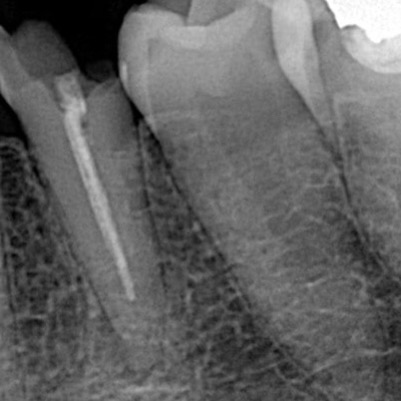

Pre- operative X ray

Obturation with Bioceramic sealer and single cone

X ray showing Obturation and Biobase

X ray after 1 year